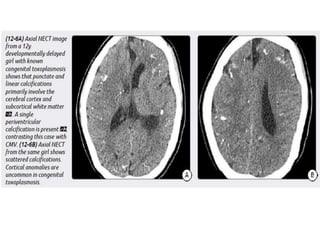

Congenital Toxoplasmosis

Imaging

Scattered parenchymal calcifications.

Multiple subcortical cysts.

Porencephaly.

Ventriculomegaly (hydrocephalus) often due to inflammatory debris and

aqueductal obstruction.

Lack of cortical malformations.

Congenital Toxoplasmosis Imaging Scattered parenchymalcalcifications. Multiple subcortical cysts. Porencephaly. Ventriculomegaly (hydrocephalus) often due to inflammatory debris and aqueductal obstruction. Lack of cortical malformations.